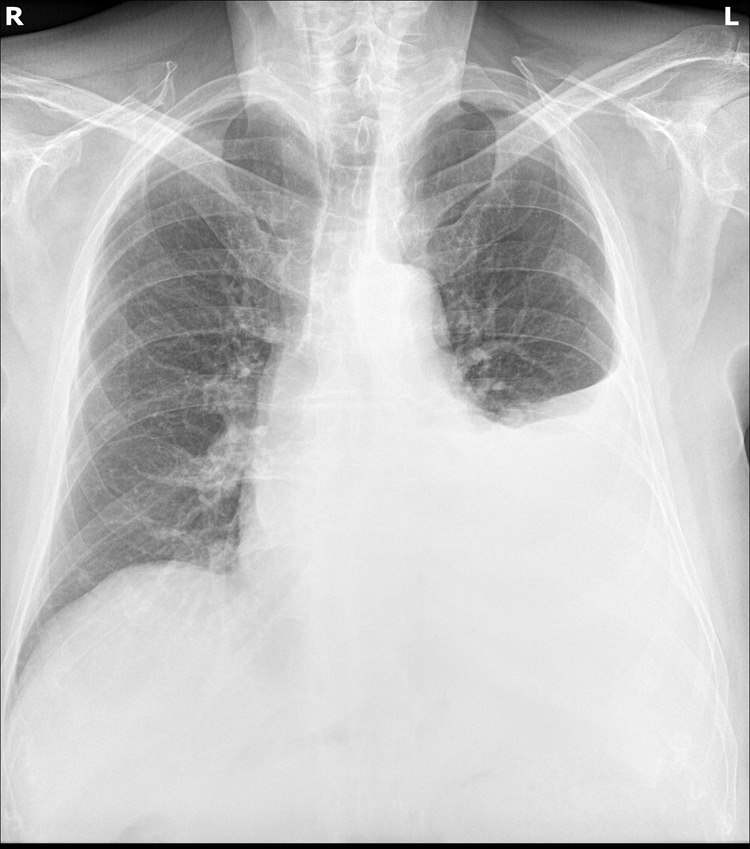

RTG klatki piersiowej

- Płyn w opłucnej można wykryć w projekcji tylno-przedniej, jeżeli obecne jest co najmniej 200 ml płynu, a na zdjęciach w projekcji bocznej już przy 50 ml płynu.2

- W przypadku nagromadzenia dużej ilości płynu może dojść do przemieszczeń w śródpiersiu.

- W ponad 80% przypadków niewydolności serca występuje obustronny przesięk opłucnowy.